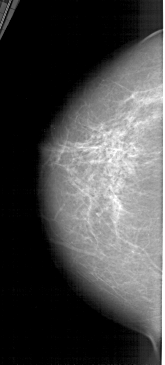

A_1424_1.RIGHT_MLO

LEFT_CC LINES 5461 PIXELS_PER_LINE 2461 BITS_PER_PIXEL 12 RESOLUTION 43.5 NON_OVERLAY